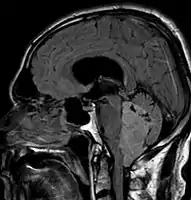

Ependymoma of 4.ventricle in MRI.